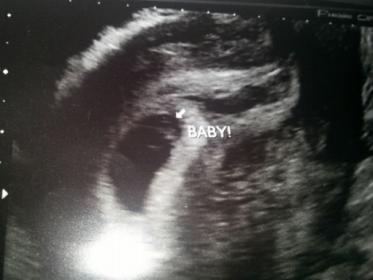

Attachment 20167

JUst curious if able to attempt ramzi and if anyone else send ad curious as I am about the black blob to the right? Have history of vanisHing twins so very curious. When did blood flow on baby it was to the right in the white part if that says anything also vaginal us. Please and thank you!